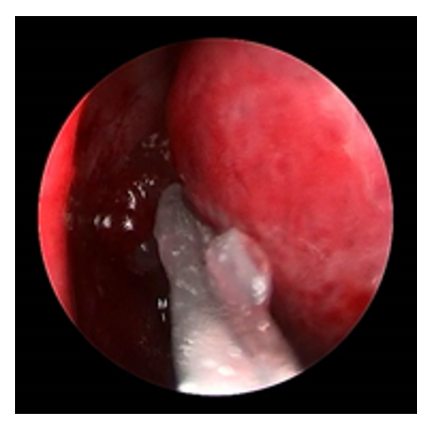

20230203160947_8339.png

图3 医用自交联透明质酸钠凝胶填充于吻合口

Figure 3 Medical self-crosslinking sodium hyaluronate gel

filling the ostium